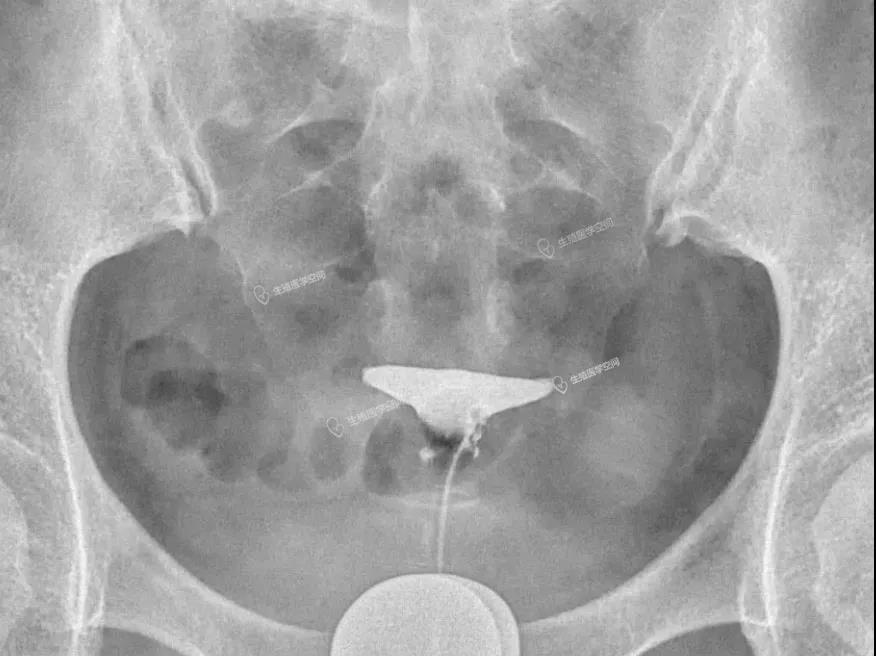

病例4 女 26岁 继发不孕,子宫输卵管造影发现双侧输卵管间质部阻塞。男方检查均正常。通过造影片初步评估介入再通术疏通成功率很高,可以达到90%左右,于是做放射科的介入再通术成功疏通了2侧输卵管。术后第5个月怀孕,后来足月妊娠,自然分娩一健康婴儿。